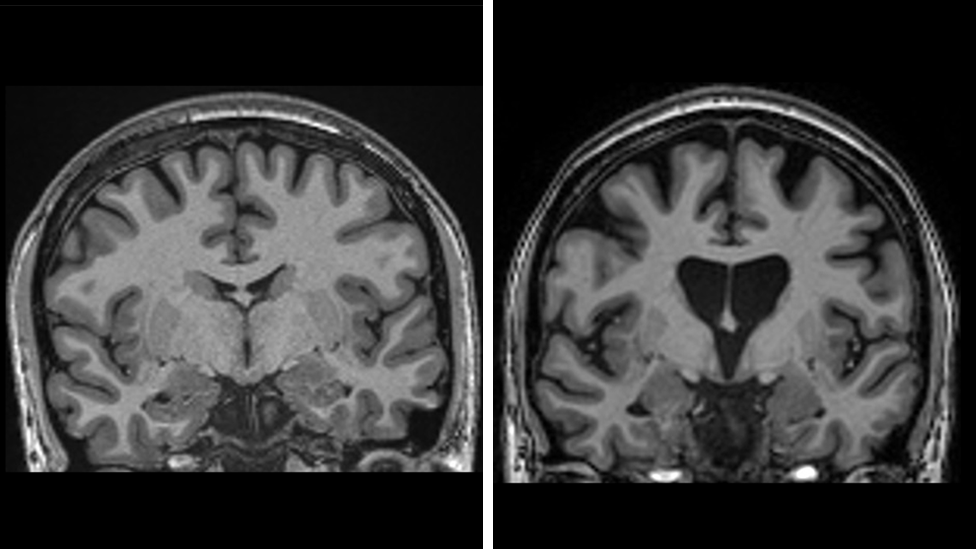

A imagem à esquerda mostra um cérebro saudável. À direita, vemos a perda de matéria cerebral, devido à morte de neurônios causada pela doença de Huntington. Crédito: UCLH

Os dados também demonstram que o tratamento está salvando as células cerebrais.